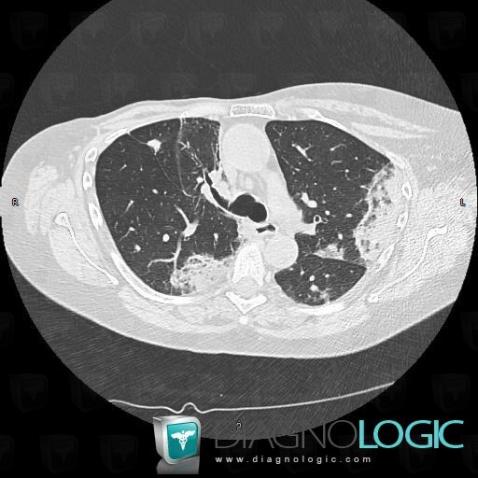

Bronchioloalveolar carcinoma, Pulmonary parenchyma, CT

Here is the specific information in the key image above:

- Diagnosis Bronchioloalveolar carcinoma, Location(s) Pulmonary parenchyma, with gamuts Multiple pulmonary nodule